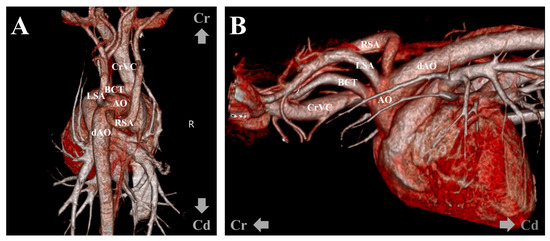

2. Case Description

3. Diagnostic Assessment, Intervention, and Outcomes